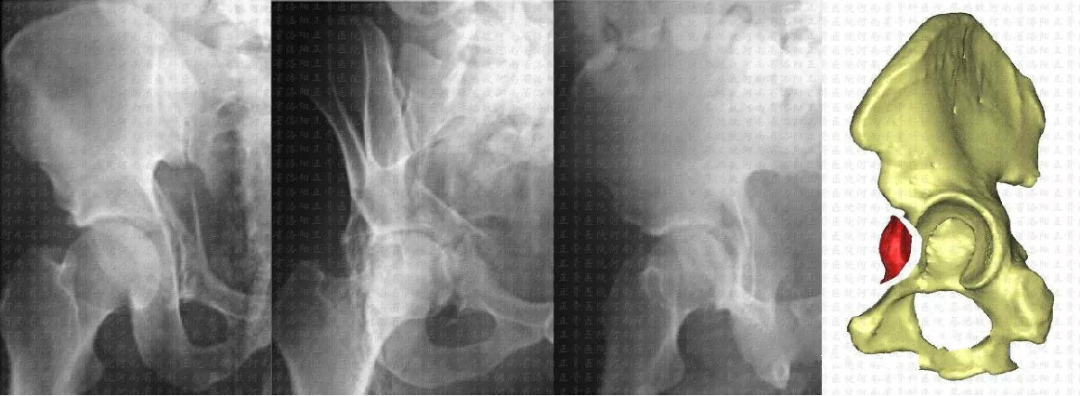

临床病例